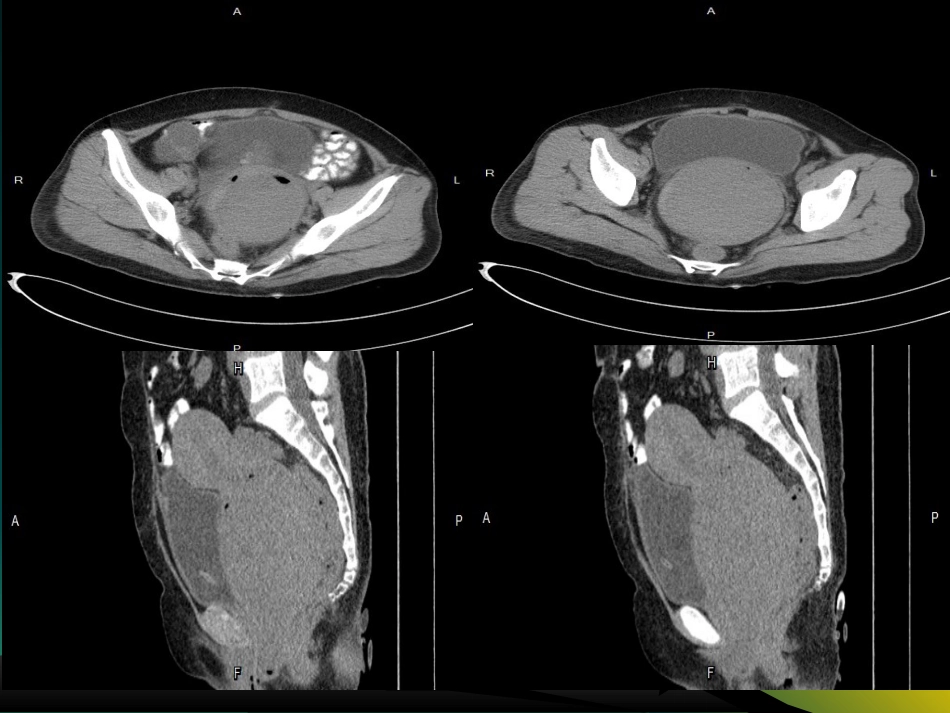

患者:张xxCT:74698性别:女年龄:42岁临床初步诊断:宫颈肿物主诉:既往抑郁病史6年,既往剖宫产史,平素月经史不规律,近半年阴道不规则流血,1天前自觉腹胀、排尿困难平扫动脉期静脉期延迟期•影像学诊断:•宫颈区软组织密度灶,考虑子宫肌瘤•右附件囊性低密度,请结合临床病理诊断:全切子宫及双侧输卵管、宫颈肿物、右卵巢肿物1.宫颈:富于细胞性平滑肌瘤伴玻璃样变性;2.右卵巢:浆液性囊腺瘤;3.增殖型子宫内膜;4.双侧输尿管组织。临床诊断:宫颈粘膜下子宫肌瘤;右卵巢囊肿、失血性贫血术中图片:子宫肌瘤:子宫肌瘤是女性生殖系统最常见的良性肿瘤之一,由平滑肌和结缔组织组成;病因:多发生于育龄妇女,绝经后肌瘤可停止生长甚至萎缩,提示可能与女性激素有关,雌激素能使子宫肌细胞增生、肥大,肌层变厚;孕激素促进肌瘤有丝分裂,刺激生长作用。病理:梭形平滑肌细胞和不等量的纤维结缔组织构成,肌细胞大小均匀,排列成漩涡状;分类:按肌瘤所在部位不同分为:1.子宫体肌瘤(95%)2.子宫颈肌瘤(5%)根据与子宫肌壁关系分为:肌壁间肌瘤、浆膜下肌瘤、粘膜下肌瘤;•临床表现:1.月经改变;•2.腹部包块•3.白带增多;•4.腹痛、腰酸、下腹追胀;•5.不孕、流产;•6.压迫症状;•子宫肌瘤生长较快时,供血不良可发生肌瘤变性,越大越缺陷严重,继发变性越明显;主要变性有几点:••1.玻璃样变:供血不足,部分组织水肿、漩涡结构消失,代以透明样物质••2.囊变:继发玻璃样变、液化坏死、液体清凉••3.红色样变:特殊肌瘤坏死,多发生产褥期或妊娠期,与局部组织缺血或栓塞所致组织出血、溶血有关,血液渗入肿瘤、生肉状;•4.肉瘤变性:恶性变;多见年龄大且生长快或伴不规则流血者、••5.钙化:多见瘤蒂细、供血不足浆膜下的肿瘤及绝经期肌瘤影像学表现:•CT:•1.子宫均匀或分叶状增大,局灶密度减低•和宫腔偏位,•2.子宫肌瘤密度均匀,边界清晰,周围脂肪层•存在,呈现良性肿瘤特征•3.发生变性,肌瘤可呈等、低、高混杂密度。•优缺点:•空间分辨率高,直观全面;分辨脂肪、出血、•钙化成分上具有一定优势;•缺点:对病变大小、数目、部位缺乏特异性;判断肌瘤变性不敏感•增强时子宫肌层和肿瘤一样显著强化,多数子宫肌瘤与正常子宫肌层密度差异不大,若无轮廓变化、小的肌瘤容易漏诊,病灶变性时,增强后不规则低密度区更为清楚,增强扫描有助于诊断及定性。MRI:1.子宫增大、轮廓凸凹不平;2.T1与子宫肌体相近、T2呈低信号,但伴坏死、液化出血等可呈高信号;3.肌瘤变性,不同病理改变,信号各异,钙化呈T1T2均呈低信号、脂肪变性则高信号;4.MRI组织分辨率高,T2可显示子宫肌层与内膜之间的结合带,呈低信号;粘膜下或肌壁间肌瘤可见结合带局灶中断或完全消失;此类病人大多数有月经过多表现;T2瘤周高信号环,常提示瘤周扩张静脉、淋巴管及水肿性改变,并常见较大肿瘤上的血管断面,T1、T2表现信号缺失区优缺点:对小肌瘤诊断率高,浆膜层、肌层及子宫内膜结构显示清楚,定位准确;鉴别诊断:•1.子宫腺肌症;二者临床表现相似,影像学均显示子宫增大,腺肌病T2也呈低信号,结合带局限性增厚或弥漫增厚,但边缘模糊,不同于子宫肌瘤界限清楚•2.子宫畸形:双子宫及残角子宫易误诊子宫肌瘤,多平面观察、寻找内膜结构能区分•3.卵巢肿瘤:整体均匀实性肿瘤罕见,多为囊、囊实性改变;4.妊娠子宫;小结•CT及MRI能够提高对肌壁间、粘膜下及多发性子宫肌瘤、小肌瘤的诊断率,更精确的显示出肌瘤的位置和内部结构,并可见观察肿瘤的周围组织情况及供血血管,为临床提供更多的疾病诊断参考价值识别图中二维码,请关注我们~!牡丹江管理局中心医院:影像中心声明:此文件仅用于交流和学习